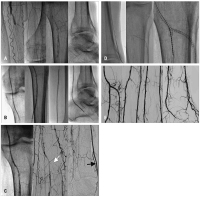

Ischämie

Abbildung 6a-e: A. Schwere chronische Ischämie im linken Bein bei Verschluß der distalen A. fem. superficialis, A. poplitea sowie sämtlicher Unterschenkelarterien, teilweise Drahtpassage bis in die A. tibialis posterior (ATP). B. PTA der A. poplitea und ATP mit einem 2,5/120 mm-Ballon. C. Zwischenergebnis; weißer Pfeil: proximaler Verschluß der A. tibialis anterior (ATA), der sich von antegrad nicht passieren ließ; schwarzer Pfeil: Auffüllung auch der A. dorsalis pedis über Kollateralen. D. Erfolgreiche retrograde Rekanalisation des Verschlusses der proximalen ATA über einen transpedalen Zugang und Stabilisierung der Unterschenkelbifurkation mittels Implantation von 3 Cypher®-Stents (2 über den pedalen Zugang, 1 Stent von antegrad). E. Ergebnis nach zusätzlicher PTA der ATP.